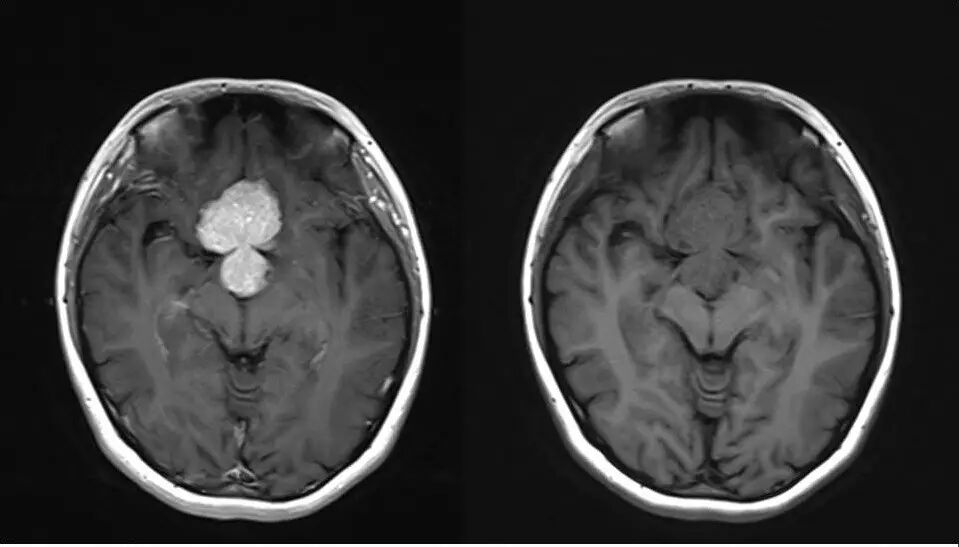

2.MR检查显示肿瘤位于鞍区,分叶状生长,呈稍长T2、稍长T1异常信号影,边界清楚,内部信号不均匀,其内可见“微囊”状异常信号影,视交叉受压上抬,DWI呈等或略高信号影,注药后呈不均匀明显强化;

5.影像表现确定肿瘤源于垂体,部位、信号、生长方式、内部结构、骨质破坏,增强显示等均符合垂体瘤诊断。